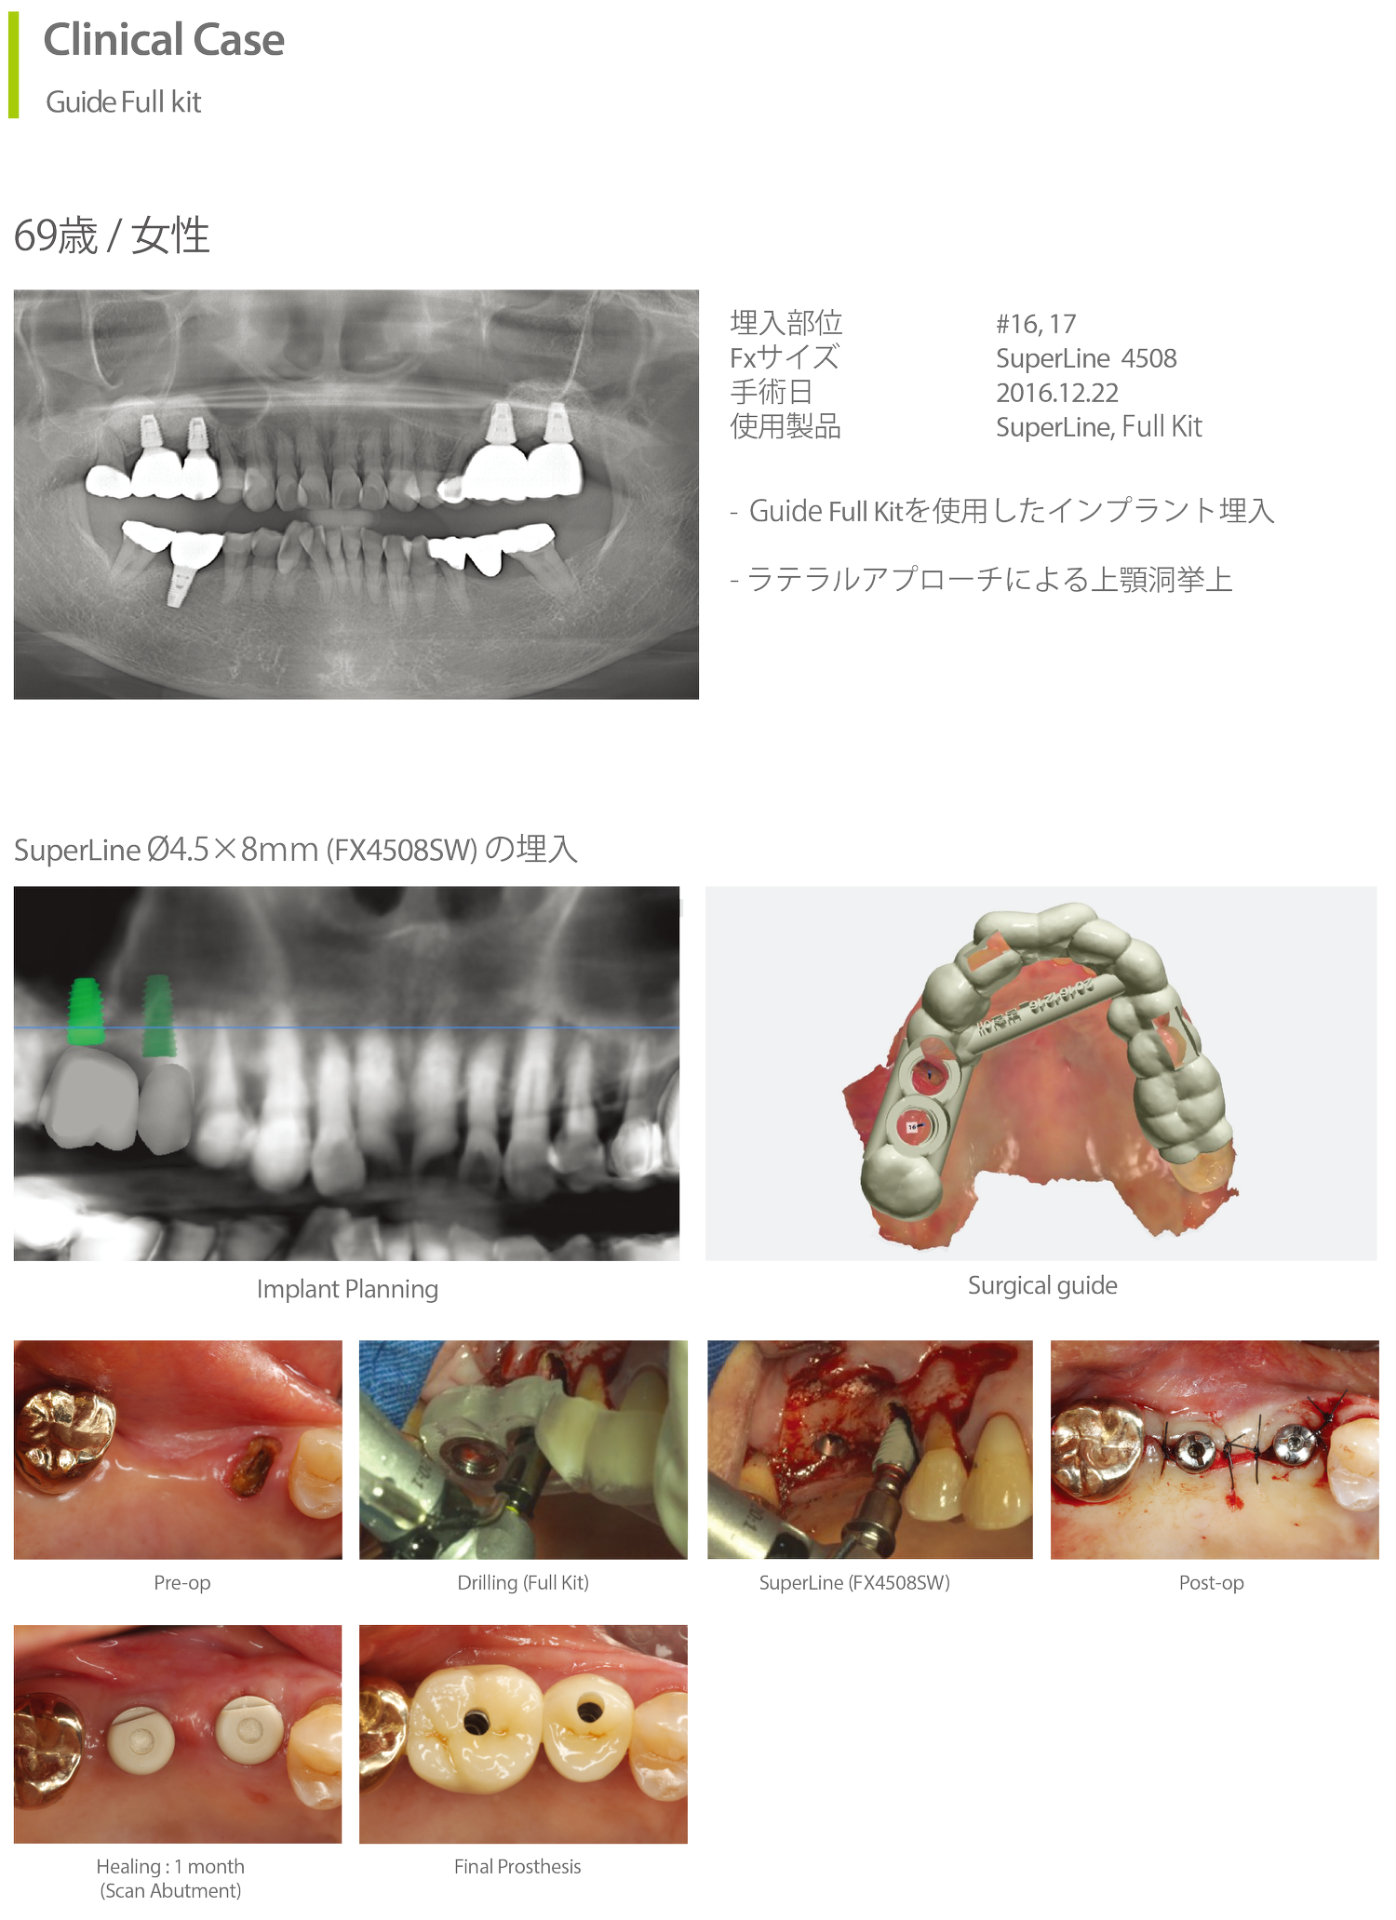

Clinical Case